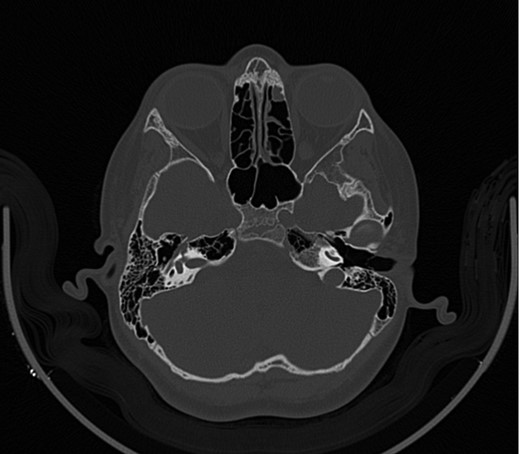

A 14-year-old male patient presented to the ENT clinic with bilateral hearing loss with no other otolaryngological symptoms. History from the patient stated a road traffic accident (RTA) 12 months ago. Meanwhile, the patient had no hearing problems prior to the RTA. Furthermore, detailed history of the accident revealed that the patient had no apparent skull injuries while pure tone audiometry (PTA) on presentation revealed bilateral conductive hearing loss and auditory brainstem response revealed right mild hearing loss and left moderate hearing loss. As a result, he was fitted with hearing aid for four months after presentation and was not compliant to it on the long-term. The patient is a non-smoker and is medically free with normal developmental milestones and negative family history of hearing complaints. Local examination of the ear revealed intact but minimally retracted tympanic membrane bilaterally. PTA was done in 2014 revealed right mild to moderate mixed hearing loss and conductive hearing loss at low frequency (Table 1). Meanwhile, the left ear had mild to moderate sensory hearing loss at high frequency (Table 2). The speech audiogram results show equal canal volume in both ears, less tympanometry pressure on the right ear and less compliance on the right ear (Table 3). The CT showed that both ossicular chains are deranged, and bilateral abnormal ossicles with no fracture or mass (Figures 1–3).

Figure 3:

CT mastoid, deranged left side ossicular disruption.